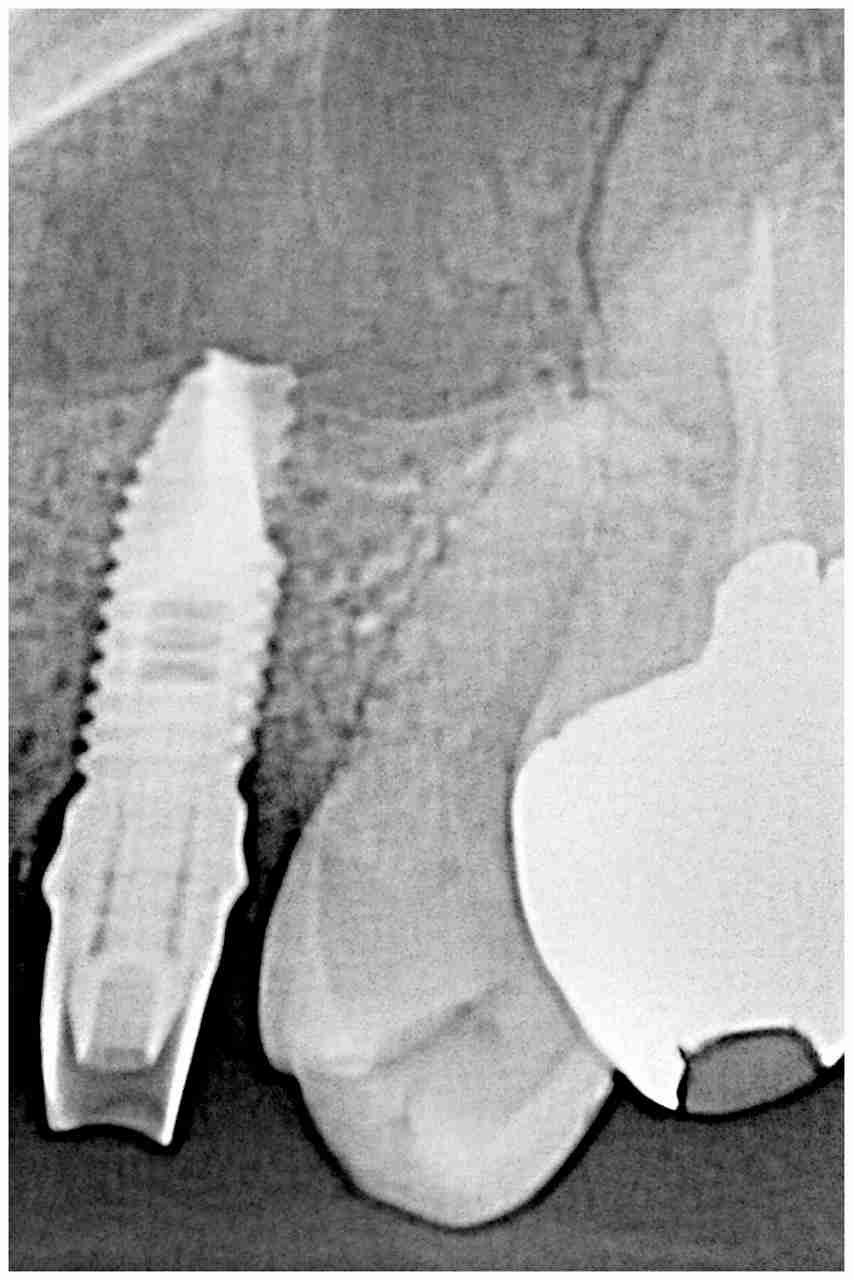

CTデータを基にインプラント設計、計画、埋入までこれを基に行っていきます。| |広島市安佐南区の歯科医院 CTデータを基にインプラント設計、計画、埋入までこれを基に行っていきます。 トップ お知らせ・ブログ CTデータを基にインプラント設計、計画、埋入までこれを基に行っていきます。 CTデータを基にインプラント設計、計画、埋入までこれを基に行っていきます。 Web診療予約 初めての方へ 選ばれ続ける理由 院内設備について 歯が痛いしみる一般歯科 歯がぐらぐらする歯周病 健康な歯を保ちたい予防歯科 子供の虫歯予防をしたい小児歯科 銀歯をセラミックに審美歯科 白い歯を目指しませんか?ホワイトニング 矯正専門医がいるので安心矯正歯科 抜けた歯を補いたいインプラント・入れ歯 医院案内 スタッフ紹介 メリィハウス歯科クリニックオフィシャルホームページ ラベンダー歯科クリニックオフィシャルホームページ お知らせ・ブログ ホーム 診療科目 一般歯科 歯周病治療 予防治療 小児歯科 審美治療 ホワイトニング 矯正歯科 入れ歯・インプラント マウスピース矯正 初めての方へ 院長・スタッフ 設備紹介 医院案内・アクセス メニューを閉じる